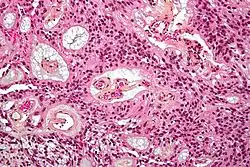

-

Micrograph of a myxopapillary ependymoma. HPS stain. -

About 10% of ependymomas are benign myxopapillary ependymoma (MPE).[8] MPE is a localized and slow-growing low-grade tumor, which originates almost exclusively from the lumbosacral nervous tissue of young patients.[8] On the other hand, it is the most common tumor of the lumbosacral canal comprising about 90% of all tumoral lesions in this region.[9]

The World Health Organization classifies ependymomas as Grade I-III. Grade I tumors are low-grade and include the subependymoma subtype, which is more common in adults. Grade II tumors include myxopapillary and conventional ependymoma, which are identified by the presence of perivascular pseudorosettes. Grade III anaplastic ependymomas are the most severe and fast-growing tumors.[4]